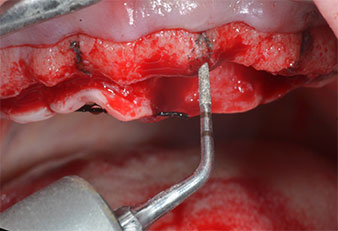

Пиезоелектрически инструмент с диамантено покритие с форма на пламък (Piezomed I1) e използван за маркиране на позициите на имплантите и за пилотна подготовка (Фиг. 3). Препарацията беше извършена с внимателни вертикални движения, с намалена мощност, пълна иригация и лек натиск (под 300 g) След това се приложи пилотен инструмент (Piezomed I2A/ I2P) за първоначално увеличение на диаметъра на имплантното ложе с 2 mm (Фиг. 4), последвано от 3 mm разширение (Фиг. 5)

Ултразву��ов пилотен накрайник за Piezomed

Фиг. 3 Препарацията с ултразвуков пилотен накрайник I1 се извършва с движение нагоре-надолу, успоредно с дългата ос на работната част.